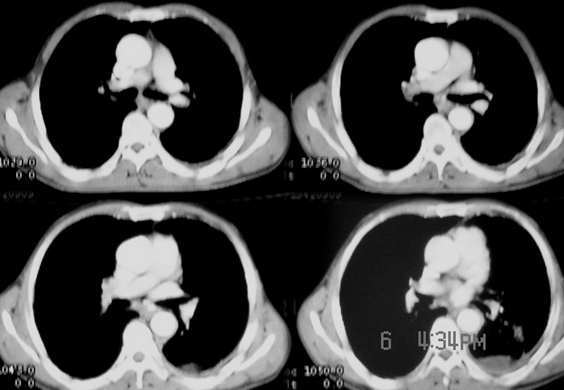

以下是引用sdqzwyx在2005-11-7 19:59:00的发言:[br]双肺弥漫大小不等的粟粒状结节影;肺纹理走行失去自然,粗细不均,边缘不规则,小叶间隔增厚;左上肺示不规则形致密影,从斑块边缘向周围伸出长短不一的致密索条影,临近的血管、支气管和叶间胸膜等结构受牵拉移位;左下肺示不规则团块状影,其内示空洞,洞内壁尚光整,左侧胸腔积液。右肺下叶背段亦示部分病灶融合。双肺可见局限性肺气肿。[br]诊断:结合病史符合三期矽肺表现(少数矽肺纤维斑块内可以形成空洞,一般认为是斑块中央感染引起坏死所致)但尘肺病人易合并肺结核,诊断可为三期+tb。所以此病人应进一步检查是否合并结核。